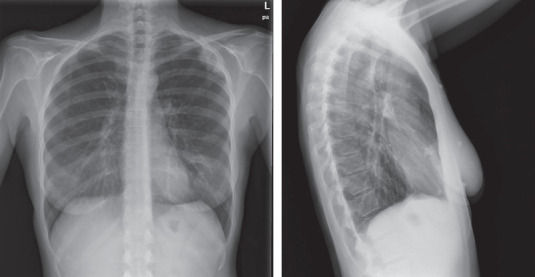

Primary Sjögren syndrome (pSS) is a systemic autoimmune disorder that principally affects the exocrine glands but can also affect systemic or extra-glandular sites. Approximately 65-80% of patients with Sjogren's demonstrate pulmonary involvement at the CT scan and pulmonary nodules (PNs) can be encountered as a common finding. We present the case of a 49-year-old woman admitted to the emergency department for chest pain and fever. The patient was diagnosed with pSS fourteen years prior and had never taken therapy or followed regular check-ups. At the HRTC were found PNs that were studied trough a CT-PET and a needle biopsy via CT guidance, which showed diffuse large B cell lymphoma. This case report underlies the importance of check-ups and the need for a multidisciplinary approach in the care of Sjögren's syndrome patients.